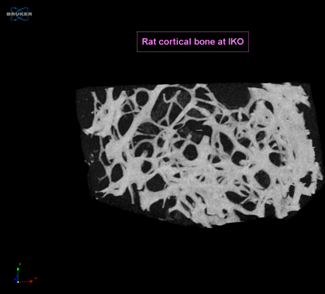

Computer Tomography is a non-destructive inspection technique based on differences in absoption of X-Rays through the material. The CT-technique provides a 3D-data set of in the sample. The attenuation of X-Rays depends on the atomic number, density and thickness of the material and on the energy of the -x-Ray beam. Non-destructive inspection of internal structure, tomodensity analysis, size and volumetric measurements are possible on the 2D as well as the 3D-images. The Skyscan 1172 is a high-resolution desktop X-Ray micro-CT system for small samples.